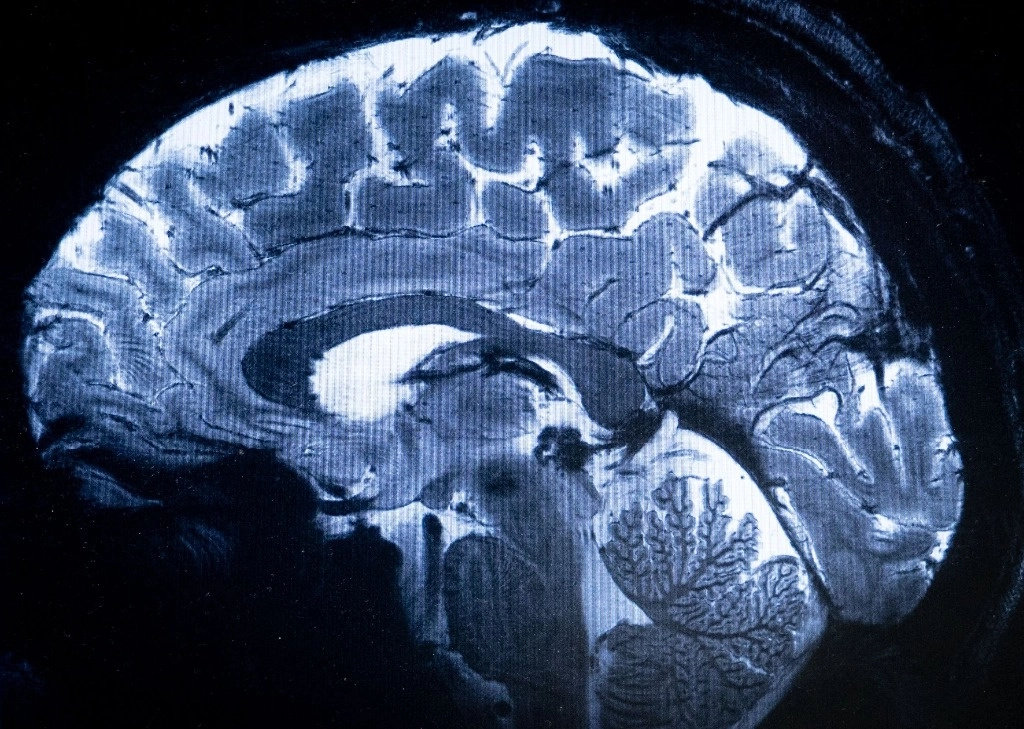

El IRM más potente del mundo muestra primeras imágenes del cerebro humano

El escáner de resonancia magnética (IRM) más potente del mundo ha logrado escanear con un nivel de precisión desconocido el cerebro humano, anunciaron sus responsables en Francia, una proeza que podría ser decisiva para detectar enfermedades. Foto Afp

"Hemos visto un nivel de precisión nunca antes alcanzado en el CEA", dijo Alexandre Vignaud, un físico que trabaja en el proyecto.

Esta potencia permite que la máquina escanee imágenes 10 veces más precisas que los IRM comúnmente utilizados en hospitales, cuya potencia normalmente no supera los tres teslas.

En una pantalla de computadora, Vignaud comparó imágenes tomadas por este poderoso escáner, apodado Iseult, con las de un IRM normal.

"Con esta máquina podemos ver los pequeños vasos que alimentan la corteza cerebral, o detalles del cerebelo que eran casi invisibles hasta ahora", dijo.